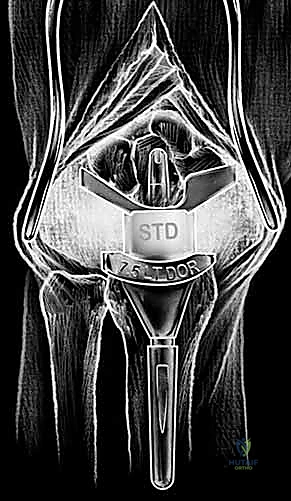

6. تثبيت المفصل الصناعي النهائي

يتكون المفصل الصناعي من جزأين رئيسيين: الجذع الكعبري (الذي يُزرع في عظمة الكعبرة في الساعد) والجذع الرسغي (الذي يُزرع في عظمة المشط الثالثة في اليد). يتم تثبيت هذه الأجزاء إما باستخدام الإسمنت العظمي الطبي، أو عن طريق الانحشار الميكانيكي الدقيق (Press-fit) الذي يسمح بنمو العظم داخل المفصل الصناعي. بين هذين الجزأين المعدنيين، توضع قطعة بلاستيكية عالية الجودة تعمل كغضروف صناعي يسمح بالحركة السلسة.